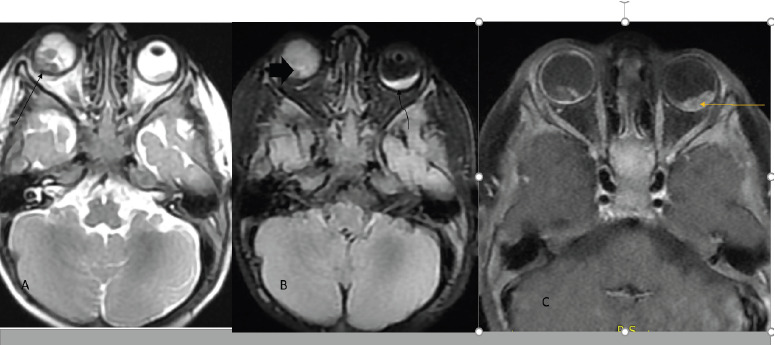

Background: Retinoblastoma is the most prevalent intraocular retinal malignancy in children worldwide. Accurate staging is critical for treatment planning and relies heavily on radiologic imaging and clinical findings. This study aims to evaluate imaging patterns and staging of retinoblastoma in children at Tikur Anbessa Specialized Hospital (TASH).

Materials and methods: This cross-sectional study analyzed retrospective data from TASH between September 2018 and September 2021. It focused on patients diagnosed with retinoblastoma who underwent Computed Tomography (CT) scans or Magnetic Resonant Imaging (MRI) and had pathology results available. Two radiologists, each with over 10 years of experience, independently reviewed the scans. Supplementary data were gathered from the pediatric oncology unit registry using structured questionnaires. The International Retinoblastoma Staging System (IRSS) was used to stage extraocular disease based on cross-sectional imaging and the International Intraocular Retinoblastoma Classification (IIRC) for intraocular disease classification.

Results: Eighty-three patients were included, with 42 (50.6%) males and 41 (49.4%) females. The mean age at presentation was 3.4 ± 2 years. The most common clinical symptoms were proptosis (42 patients, 50.6%) and leukocoria (37 patients, 44.6%). Clinical staging revealed 63 (75.9%) patients in Group E, 19 (22.9%) in Group D, and 1 (1.2%) in Group C according to IIRC. Stage IV disease was predominant, with 33 (39.2%) in Stage IVA and 18 (21.4%) in Stage IVB according to IRSS.